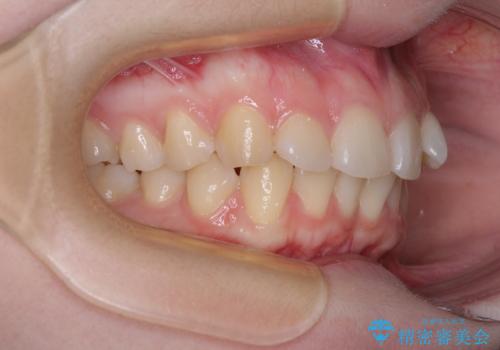

- 左上の前歯が出ていることを主訴として来院された患者様です。

当初はインビザラインを希望されていましたが、職業柄お茶する機会が多く装着時間を確保することが難しいとのことで、相談の上ワイヤー矯正の中では目立ちにくい審美装置で矯正を進めていくこととしました。

1年と少しで矯正治療を終えることができ患者様は大変満足されました。